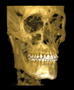

Documentações Ortodônticas

É um conjunto de exames (radiografias, fotografias , análises, modelos) que são imprescindíveis para que juntamente com a anamnese, exame clinico, exame funcional seja feito o diagnóstico e planejamento ortodôntico .Além disso, servem como um registro para comparação e avaliação dos resultados do tratamento ortodôntico e como documentação legal.